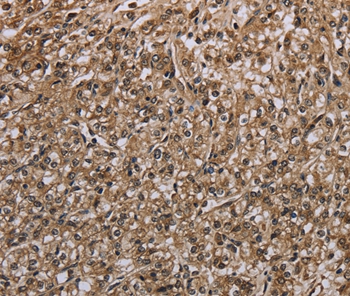

Immunohistochemical analysis of paraffin-embedded Human prostate cancer tissue using #37748 at dilution 1/20.

Immunohistochemical analysis of paraffin-embedded Human brain tissue using #37748 at dilution 1/20.